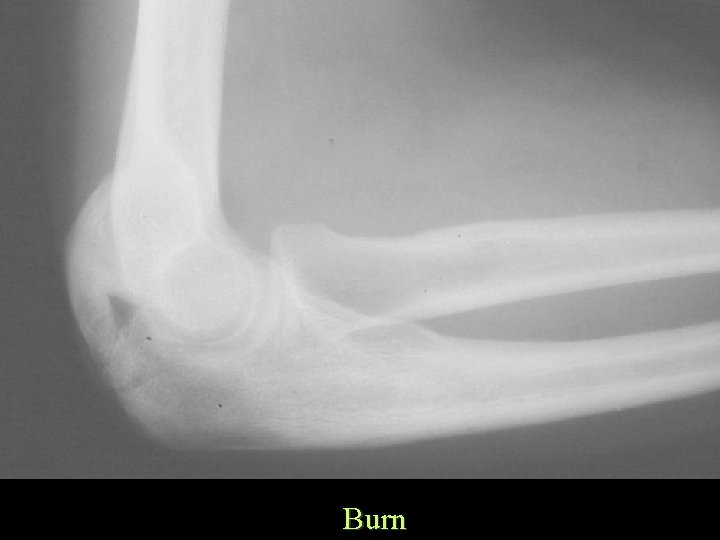

Ossification Traumatic Burns • Commonly elbow • Occurs distal to burn

Burn